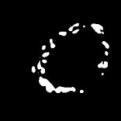

To better retain the deep features of an image and solve the sparsity problem of the end-to-end segmentation model, we propose a new deep convolutional network model for medical image pixel segmentation, called MC-Net. The core of this network model consists of four parts, namely, an encoder network, a multiple max-pooling integration module, a cross multiscale deconvolution decoder network and a pixel-level classification layer. In the network structure of the encoder, we use multiscale convolution instead of the traditional single-channel convolution. The multiple max-pooling integration module first integrates the output features of each submodule of the encoder network and reduces the number of parameters by convolution using a kernel size of 1. At the same time, each max-pooling layer (the pooling size of each layer is different) is spliced after each convolution to achieve the translation invariance of the feature maps of each submodule. We use the output feature maps from the multiple max-pooling integration module as the input of the decoder network; the multiscale convolution of each submodule in the decoder network is cross-fused with the feature maps generated by the corresponding multiscale convolution in the encoder network. Using the above feature map processing methods solves the sparsity problem after the max-pooling layer-generating matrix and enhances the robustness of the classification. We compare our proposed model with the well-known Fully Convolutional Networks for Semantic Segmentation (FCNs), DecovNet, PSPNet, U-net, SgeNet and other state-of-the-art segmentation networks such as HyperDenseNet, MS-Dual, Espnetv2, Denseaspp using one binary Kaggle 2018 data science bowl dataset and two multiclass dataset and obtain encouraging experimental results.